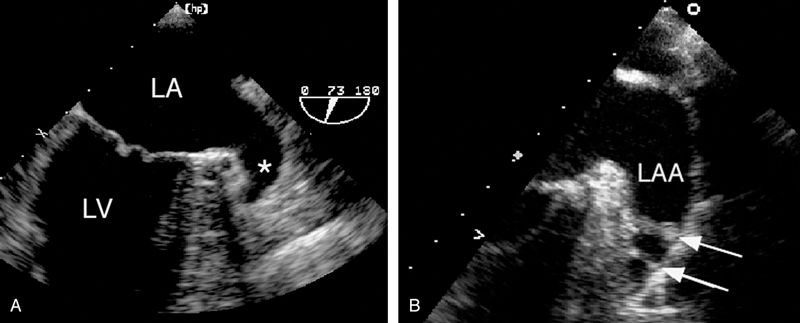

فحوصات تشخيصية لبعض امراض القلب والشرايين التاجية